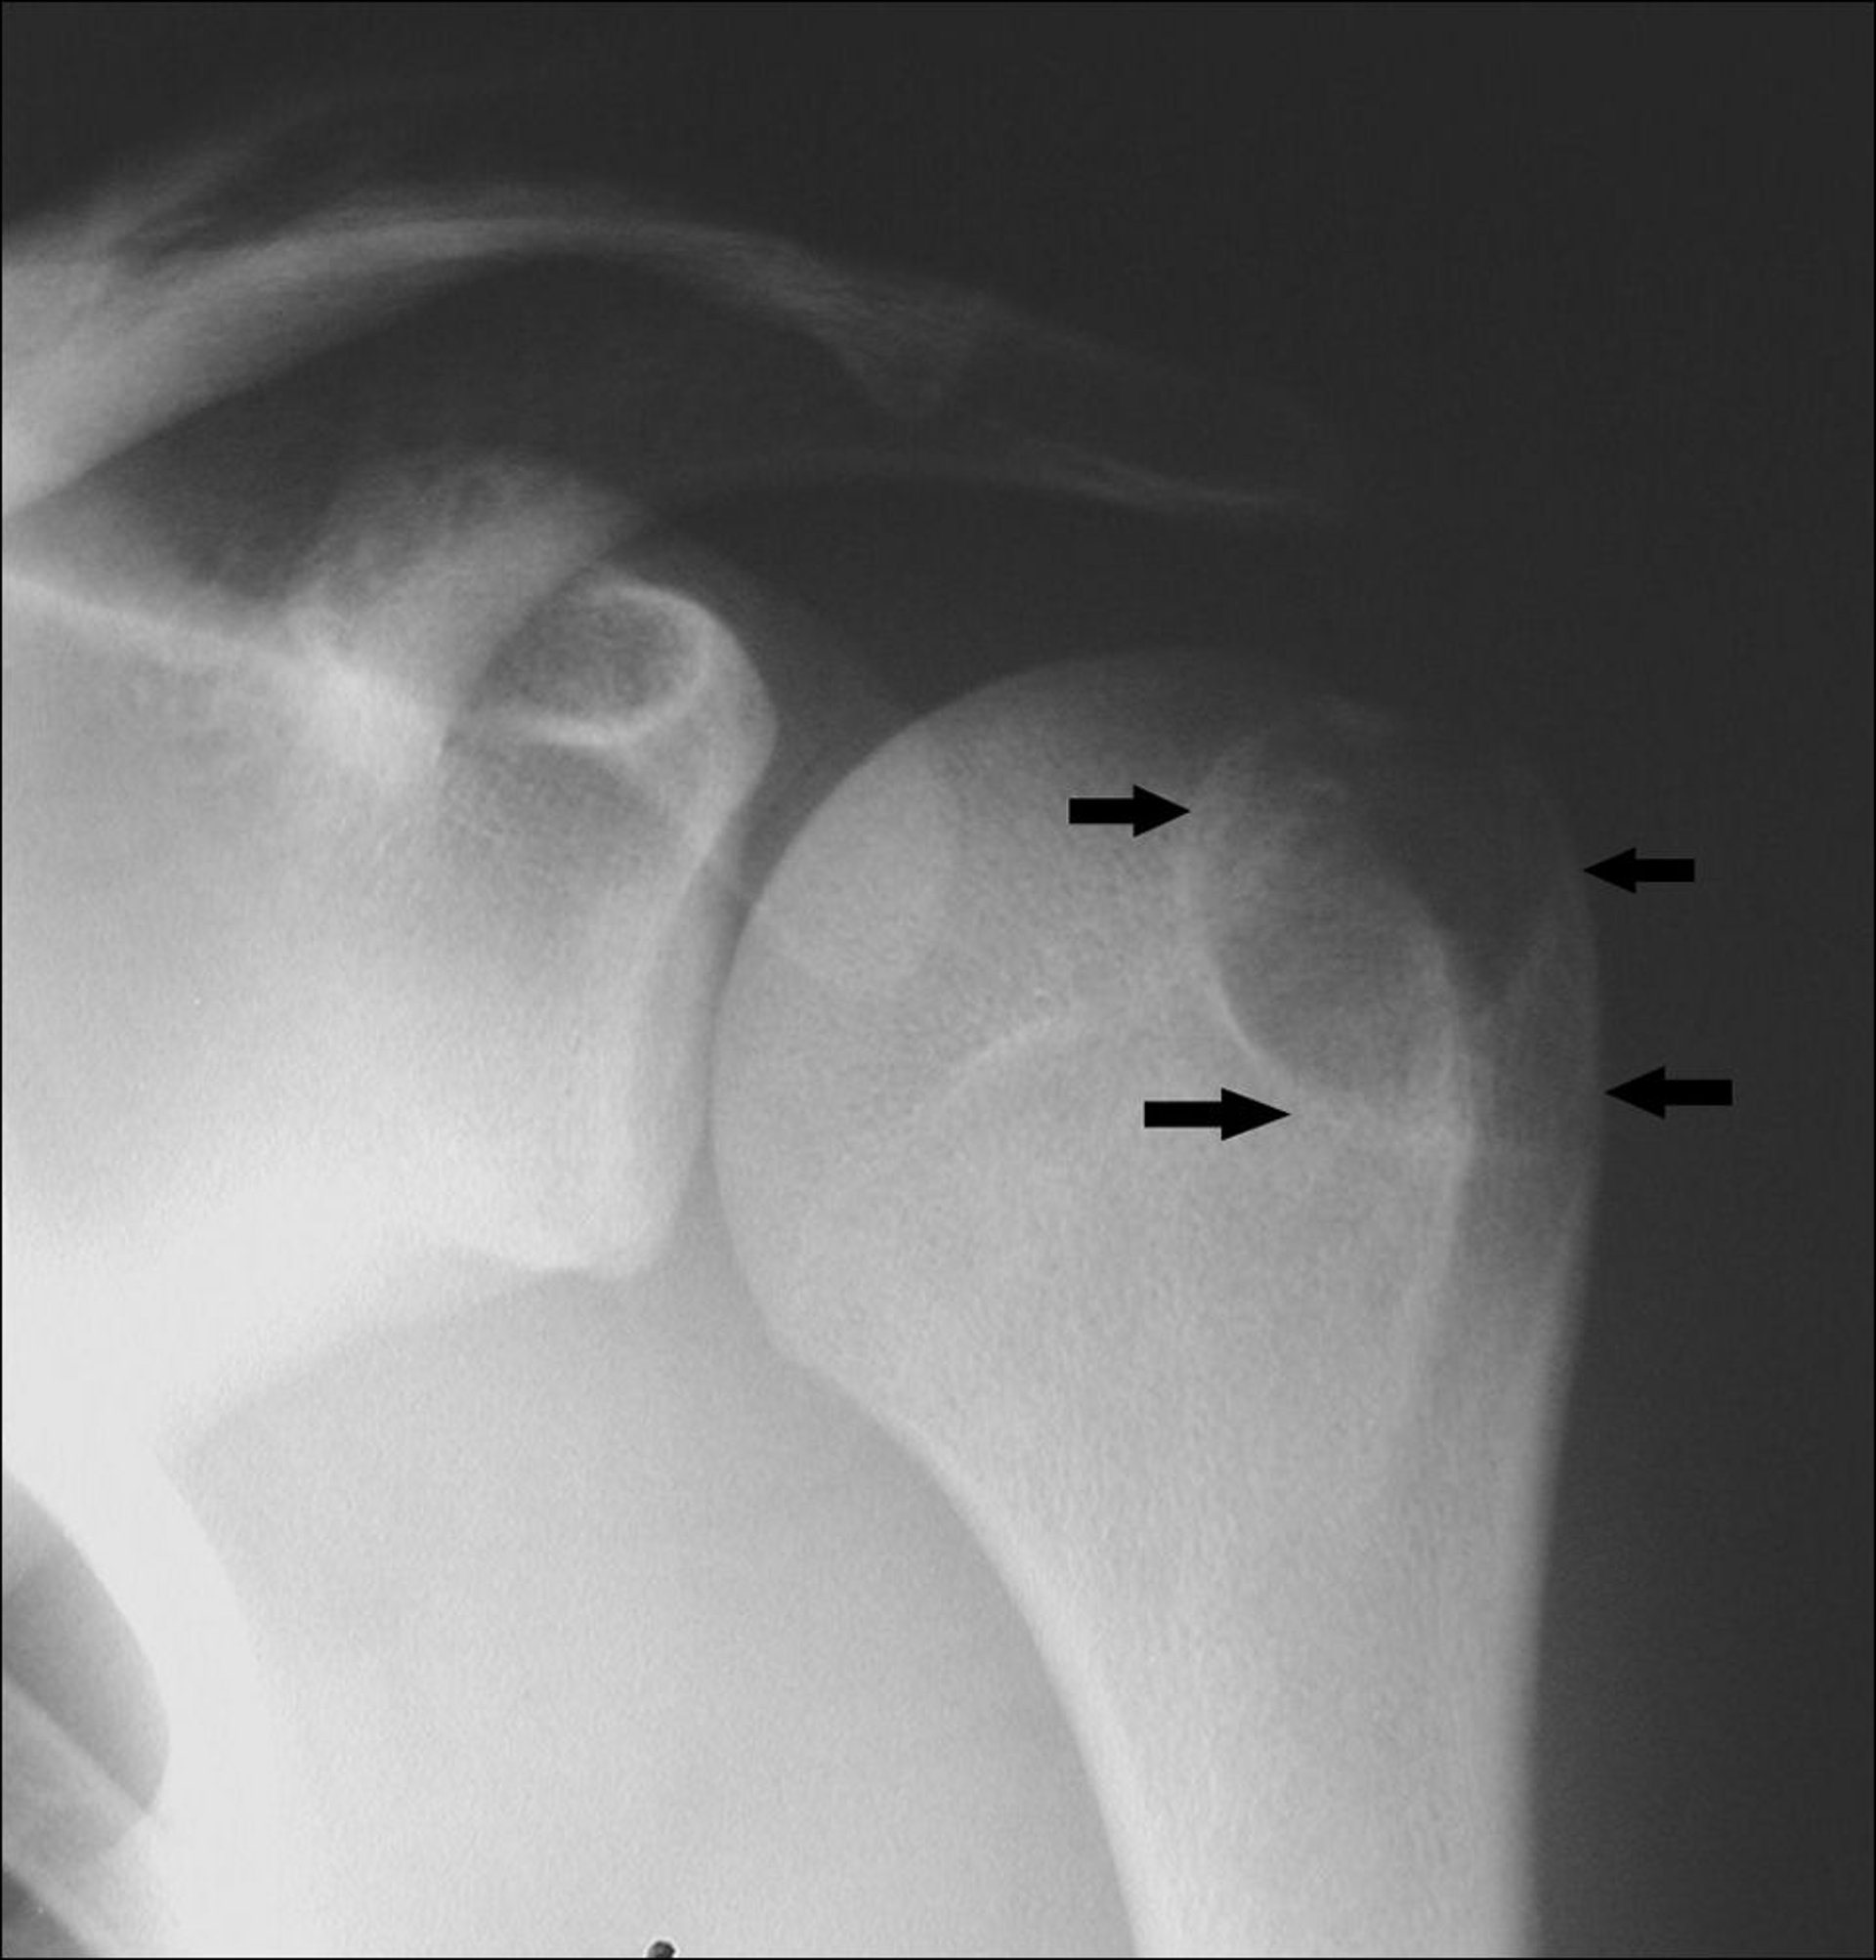

Diese Schulter-Röntgenaufnahme zeigt ein Chondroblastom im Humerus an der Apophyse des Tuberculum majus (Pfeile).